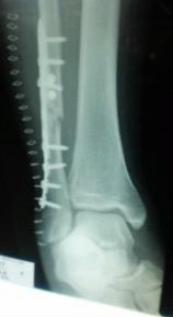

後書きですいません1月4日弟の手術が無事終わりました病院の都合で手術が4日までのびました「年末年始で先生の都合が合わないんです」ということでした 怪我して救急車を呼んだ弟1軒目の病院には断られしばらく電話で救急隊員の方が探してくれた病院年末年始だっつぅ--のにありがとうございますしかも当直でもない先生がわざわざ来てくれて脱臼はその場ではめてくれたそうです 診断結果は脱臼骨折担ぎこまれすぐにとったレントゲン写真なんて笑えるくらいよく出来た脱臼らしい脱臼とこれぞ!骨折!という見事な折れっぷりの写真でした(これを撮るのを忘れました(;゚(エ)゚) アセアセ) 手術は右足関節脱臼骨折 観血的整復固定術チタンプレ-トinですよ♪15cmくらいの切開で足がファスナ-みたいになっていましたヾ(〃゚ー゚〃)ノヾ(〃。。〃)ノヾ(〃゚ー゚〃)ノヾ(〃。。〃)ノうんうん今のこの足だったら金属探知機にキンコンカンコン♪かな? ま…とにかくこのくらいで済んでよかったです頭とか打ってたらこんなもんじゃすまなかったはず

あとがき日記です… 今日は担当の先生から家族に手術説明がありました腓骨がパッキリ折れてるためこれは確実にチタンプレ-トでつなぐこと確定♪(*^^)/。・:*:・゚'★,。・:*:・゚'☆ Congratulations!!で…脛骨は…内果部分が折れてはいるんだけどとめるまで行かないんじゃないか…というレントゲンでの目視での見解開けてみて必要であればボルトでつなぎますとのこと… 脱臼部分も綺麗に入ってるし腓骨だけプレ-トでつなぐだけならそんなに時間はかかりませんとのこと♪後は靭帯は切れてるのはしょうがないつながるまで待ちましょうってことで時間が解決してくれるのかな?骨がソコソコくっつくのに3ヶ月術後のリハビリを始めるのも2~3ヵ月後からかな?